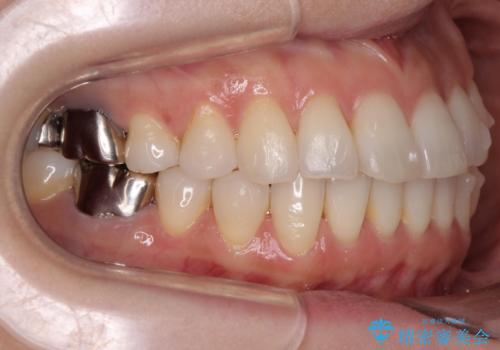

抜歯をせず前歯の角度を改善するマウスピース矯正治療

- 突き出た前歯の角度を改善したい、と矯正治療を希望され来院されました。

抜歯を行いワイヤー矯正で2-3年程度の時間をかけて、しっかり前歯を後方に移動させるか、

抜歯を行わずにIPR(歯の間に空隙を設ける)で可及的に角度の改善を行うか、

2通りの治療方針をご提案しました。

治療期間が約半年で行うことができ、歯を抜かずにマウスピース矯正で可及的に前歯の角度を改善する治療方針を

奥歯の状態等も鑑みて選択されました。

約半年で大きく前歯の角度を改善することができ、抜歯を行わない矯正治療の結果に大変喜んでいただくことができました。